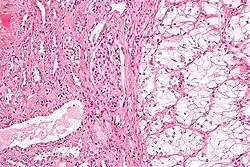

Bronchoalveolar carcinoma | Lepidic pattern of growth of tumor cells along the alveolar wall resembling butterfly sitting on fence. Normal alveoli is seen towards right side. | Category: Histopathology of bronchio-alveolar carcinoma | Bronchio-alveolar carcinoma |

![]() |